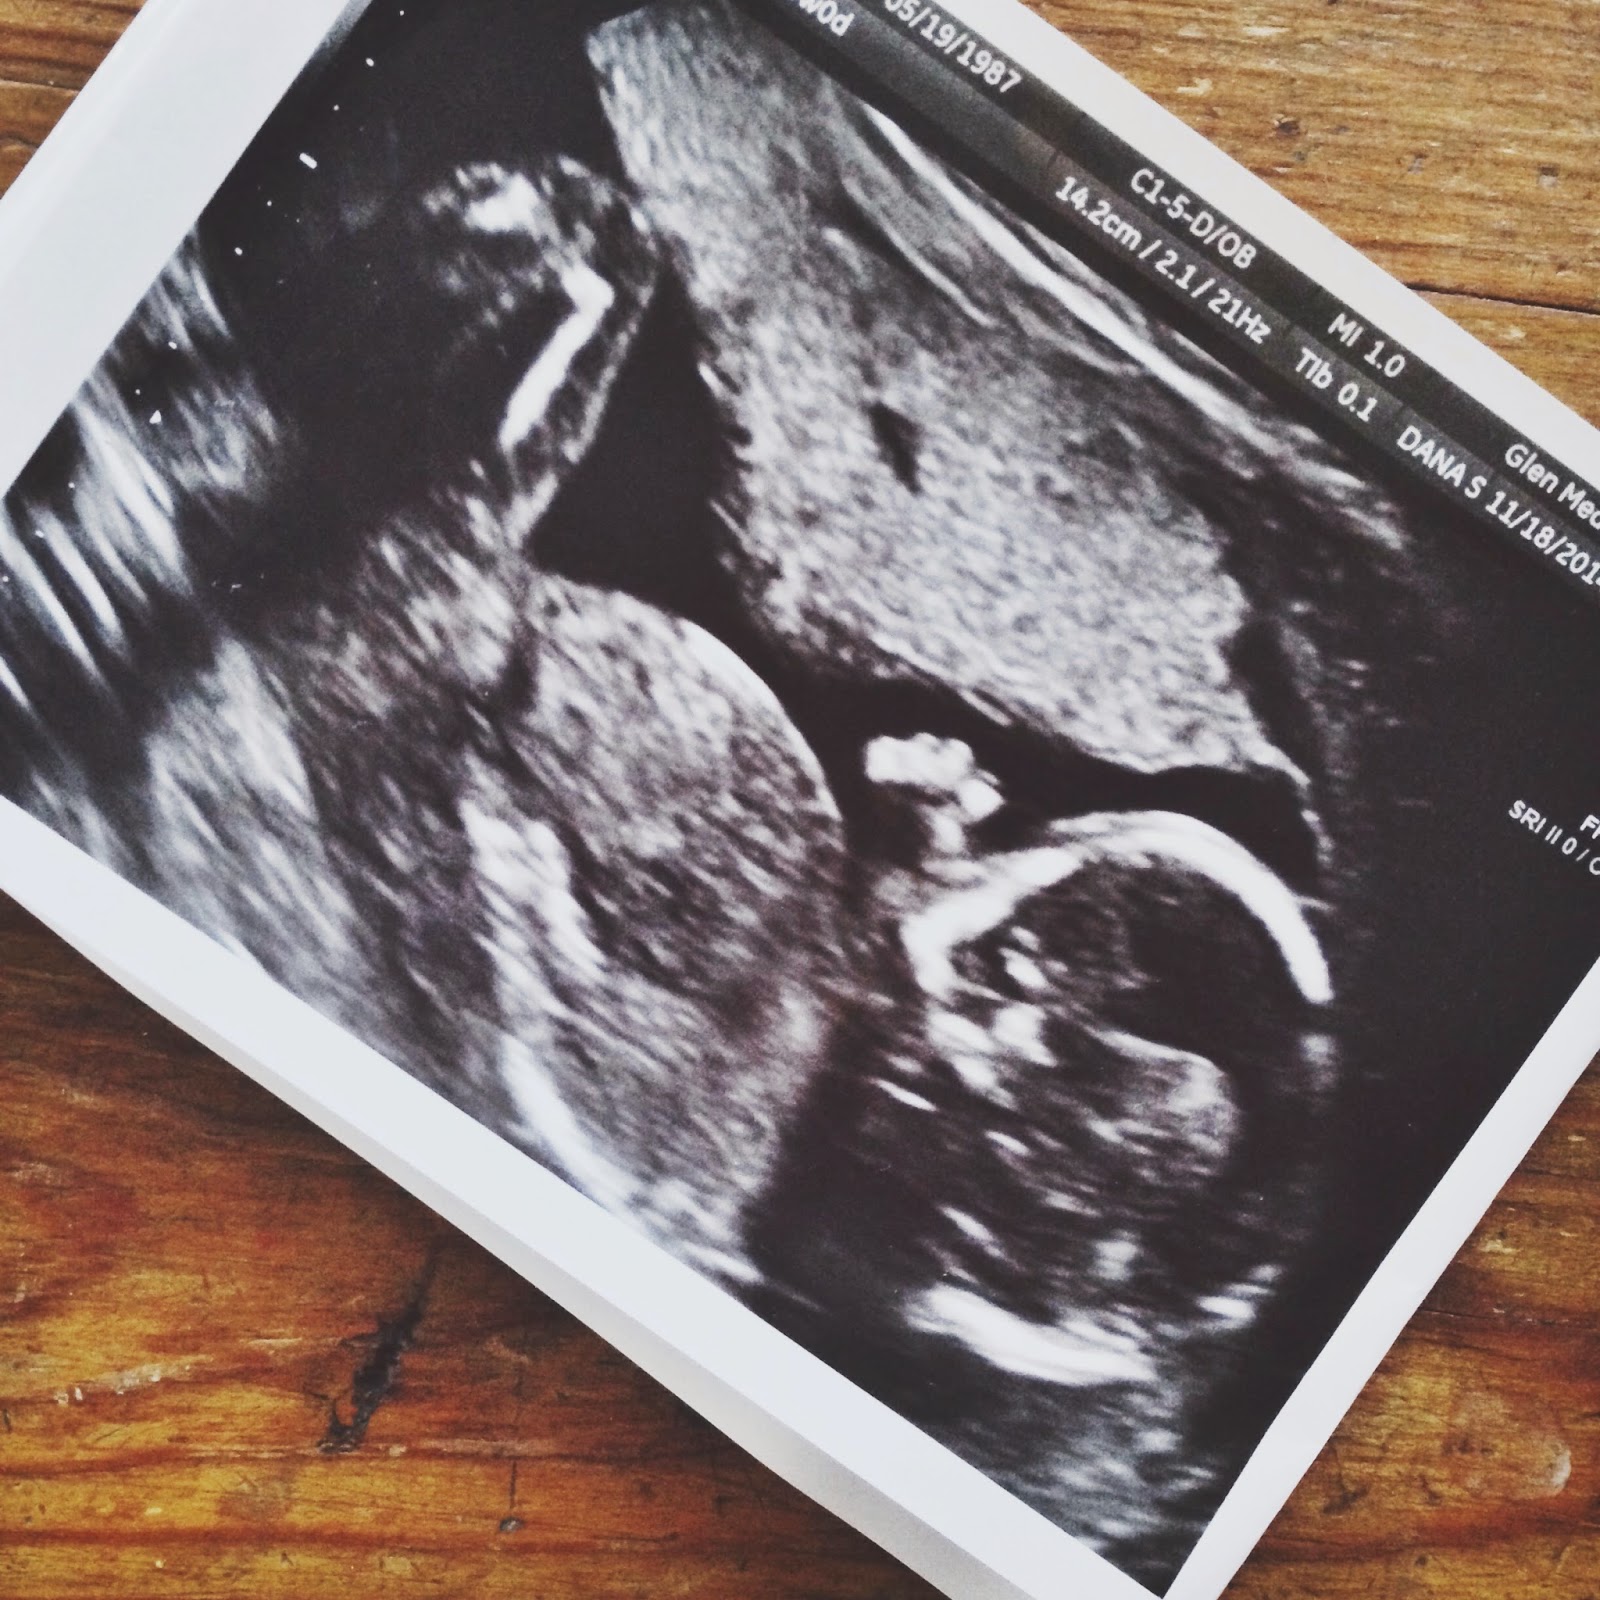

Ультразвуковое исследование (УЗИ) является одним из наиболее распространенных методов диагностики в медицине. Во время УЗИ врач использует специальный аппарат, называемый ультразвуковым сканером, чтобы создать изображение внутренних органов и тканей пациента.

Для получения фото УЗИ пациенту обычно предлагается лечь на специальный стол в позиции, наиболее удобной для проведения исследования. Врач наносит гель на кожу в области, которую необходимо исследовать, и затем прокатывает ультразвуковую головку по поверхности кожи. Ультразвуковые волны проникают внутрь органов и тканей, отражаются от них и возвращаются обратно к ультразвуковой головке, где преобразуются в изображение на экране.

Фото УЗИ могут быть черно-белыми или цветными, в зависимости от настроек ультразвукового сканера. Они могут быть сохранены в цифровом формате для последующего анализа и диагностики.